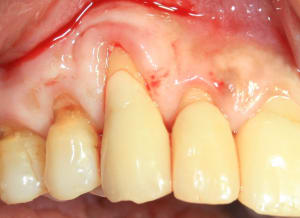

12_jours_post-op_yq86sa.jpg